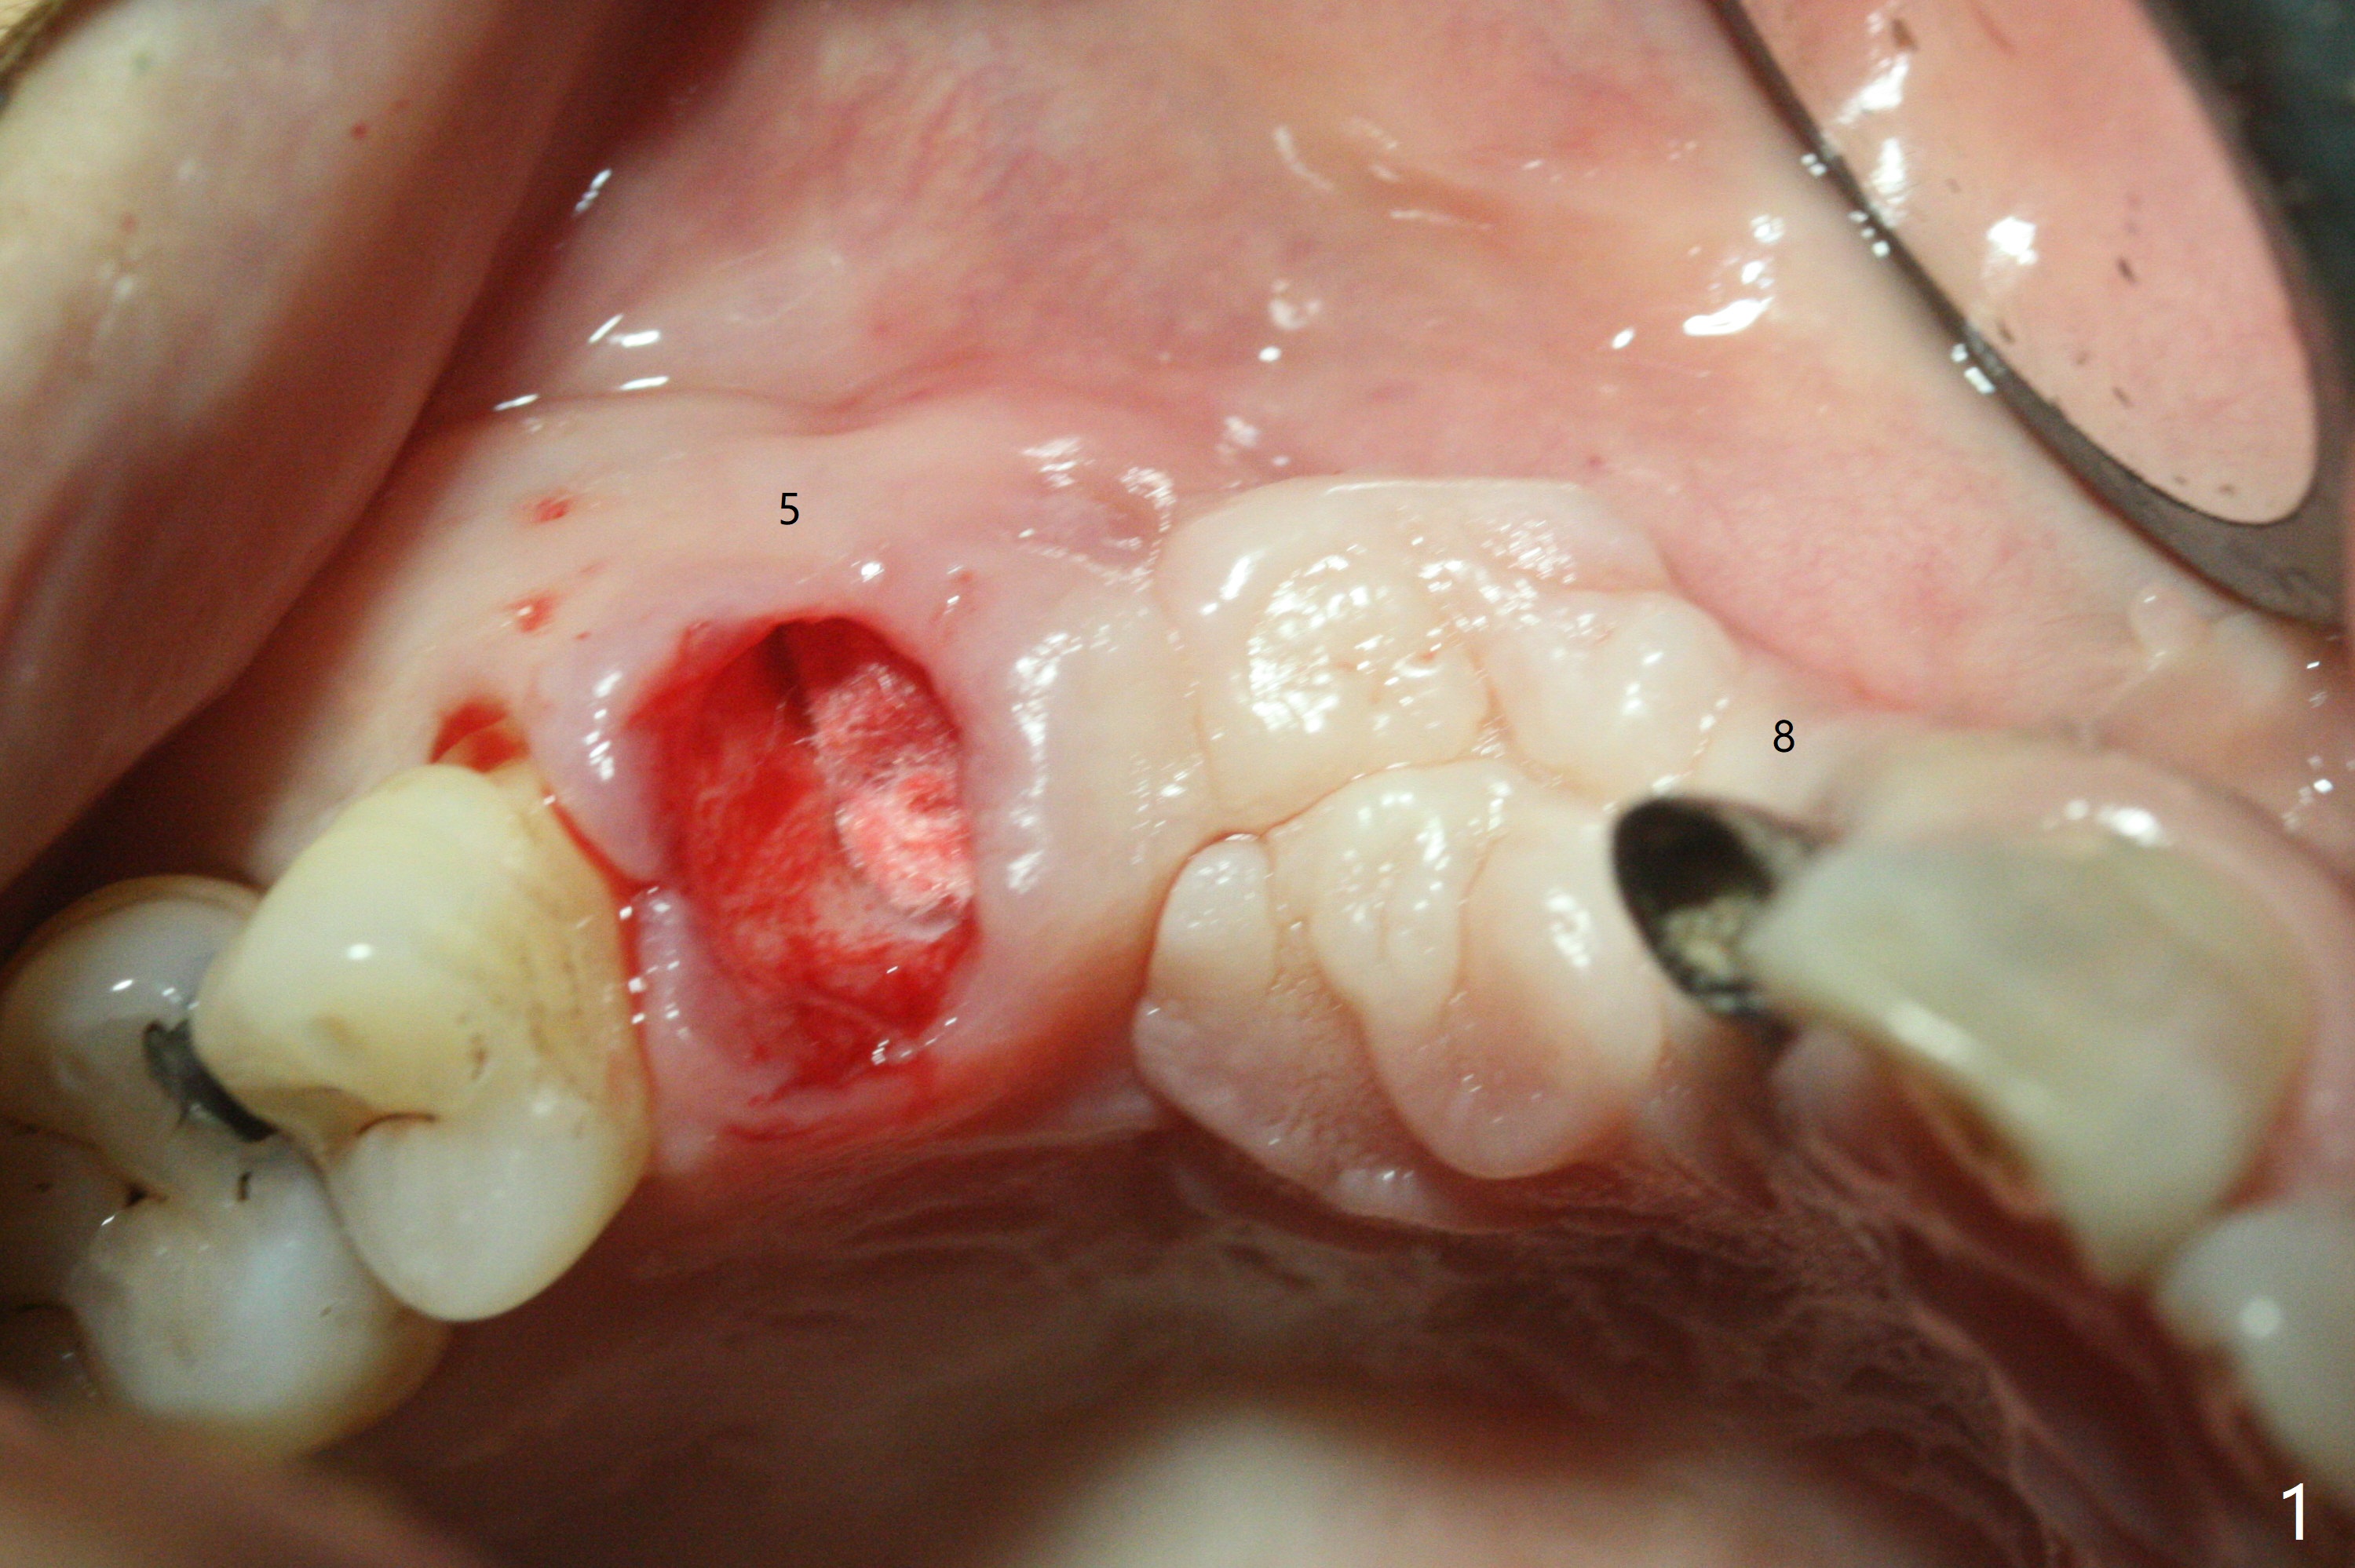

这个病例材料送到实验室作导板,实验员实在为难,只好徒手做。五号牙拔除证实颊侧骨板完全丧失,应该做位点保留(图一),但是病人非常恐惧,颊舌侧向牙槽窝好像很宽,开始尽量在舌侧建立钻洞,好像舌侧骨板太薄,又在稍微颊侧钻洞(图二),使用简易suction down stent控制钻洞方位。钻头大时,颊侧根尖有震动感觉,当时不明白为什么,稀里糊涂的植入3.8乘13毫米植体,扭力低,唯一欣慰的是颊侧放置PRF膜和粘性骨似乎到位(到根尖;图三:S),放置基台时,下面植体一起旋转,木已成舟,再次在基台周围放置骨粉。